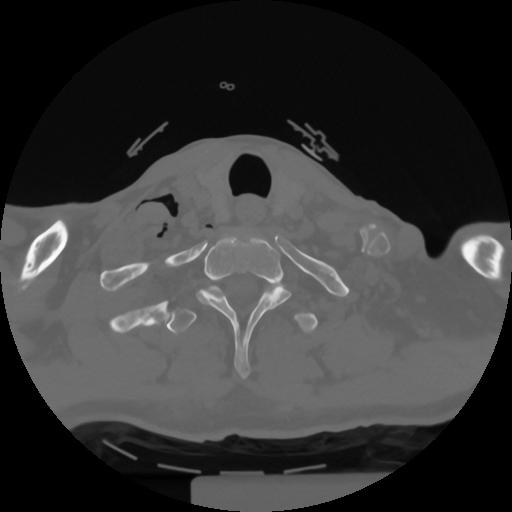

12 P.BLANDAS,,Vol,0.5,P.BLANDAS,,